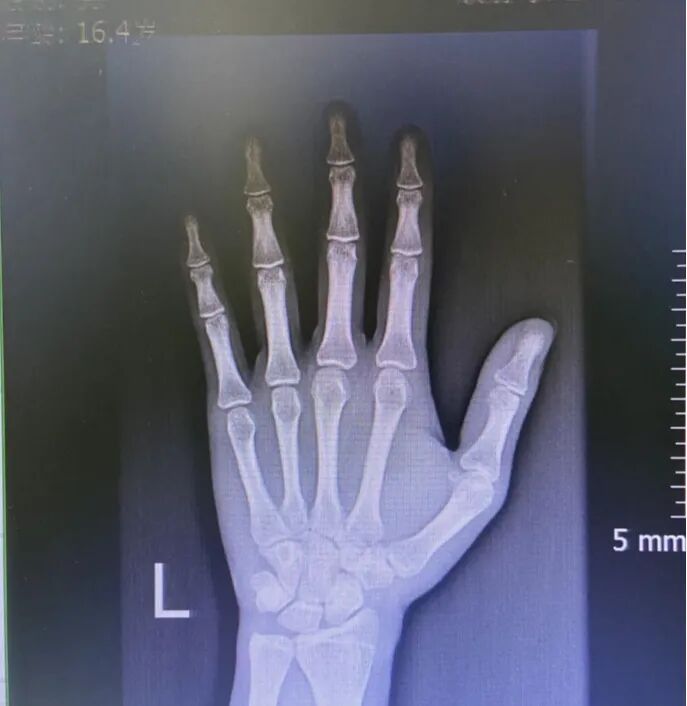

▲小杨的骨干骺端接近闭合

我们看下还有生长空间的孩子生长板是什么样的:

▲左图为4.7岁孩子的生长板,清晰可见

右图为17岁男孩,骨干骺端完全闭合,生长板消失